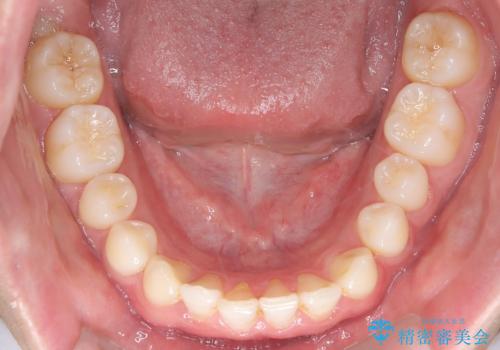

- 主訴:上の歯列の空隙を閉じたい

上顎前歯部に空隙が目立ちました。ワイヤー矯正、インビザライン(マウスピース矯正)どちらの方法でも適用症例と説明し、ワイヤー矯正治療(審美装置)を希望されました。

上顎歯列の空隙を閉じるのと一緒に、ディープバイト気味の被蓋も下顎前歯の圧下を行い改善しました。